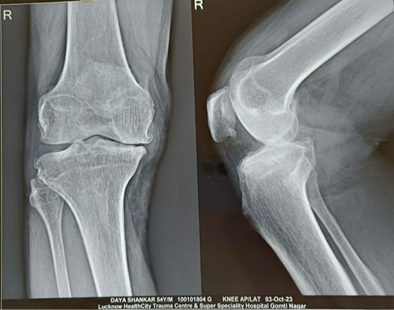

Uni-compartmental knee replacement (UKR), known as partial knee replacement, is a surgical intervention focused on replacing solely the impaired surfaces of one compartment of the knee (Medial or Lateral), typically caused by severe arthritis. During this procedure, metal and plastic implants are employed to resurface the damaged cartilage and underlying bones in a specific area of the knee.

Partial knee replacement (UKR) is typically recommended for individuals who meet the following criteria:

Advanced arthritis localized to one side of the knee, either the medial (inner) or the lateral (outer) side Intact ligaments, good mechanical stability, and a satisfactory range of motion in the knee Healthy cartilage and bones in the non-affected compartments Have exhausted conservative (non-surgical) treatments, such as lifestyle adjustments, pain relief medications, knee exercises, weight management, cartilage supplements, and lubrication injections Experience worsening symptoms despite the aforementioned measures, or encounter significant adverse effects from medications.